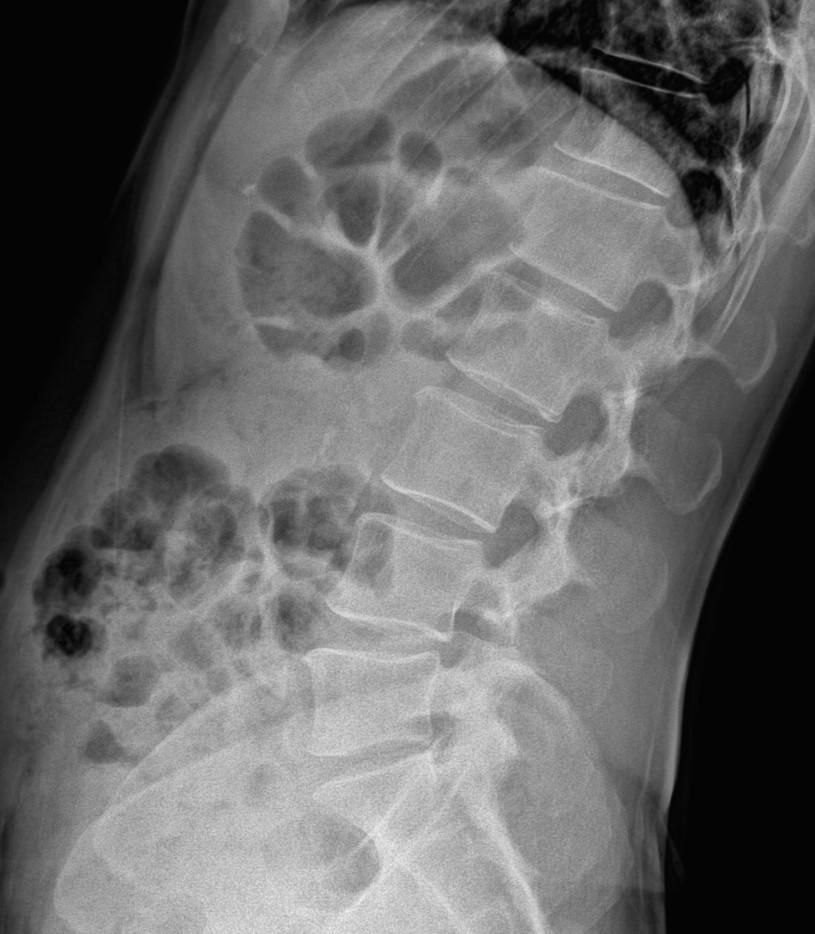

• 2번 째 사진

엑스레이 상에서는 요추 배열이 전반적으로 잘 유지돼 보입니다. 마나 일부 요추 간격이 좁아진 부위가 있어 보입니다. 말씀하신 것처럼 특정 동작에서 찌릿 혹은 뜨끔하거나, 최근 뻐근함이 생기는 건 디스크 초기나 근육, 인대 긴장에서도 나타날 수 있습니다.

허리의 커브가 줄어들어있다는것을 제외하고는 크게 문제가될만한 부분은없는데요 통증과불편감이 지속된다면 MRI와같은 정밀검사가 필요할수있습니다

사진상 요추 사이의 간격이 다소 좁아 보이며 간격이 좁다는 것은 퇴행성 변화를 의미하며 척추의 정렬 또한 큰 전위는 없어 보이나 허리 곡선이 정상보다는 조금 감소한 상태로 이러한 경우 근육의 긴장이나 만성적인 통증이 발생할 수 있습니다.

• 엑스레이 검사를 통해서는 현실적으로 뼈 위주의 평가만 가능하며 정밀하고 자세하게 평가를 내리는 것은 어렵습니다. 올리신 엑스레이 사진들에는 특별히 문제가 있다고 볼만한 소견이 크게 있어보이거나 하지는 않습니다.

우선 현재로썬 척추와 척추 사이인 디스크 공간이 좁지는 않아보이지만 다소 요추의 커브가 감소되어 있어 보입니다.